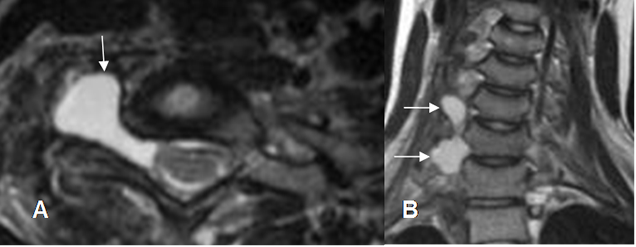

La ausencia de la raíz es el principal signo de ruptura (4). La avulsión de una raíz ocasiona seudomeningocele, por ruptura de la aracnoides y la duramadre. Se identifican en las secuencias de T2, como una lesión de consistencia quística que rodea la raíz. (1, 3).

Identificar un seudomeningocele traumático es un signo de lesión preganglionar, pero no patognomónico. (4). (Fig 9).

Fig 9. Ruptura de raíces.

A: RM axial y B: RM coronal en STIR. Formación de seudomeningocele derecho, por avulsión de las raíces.